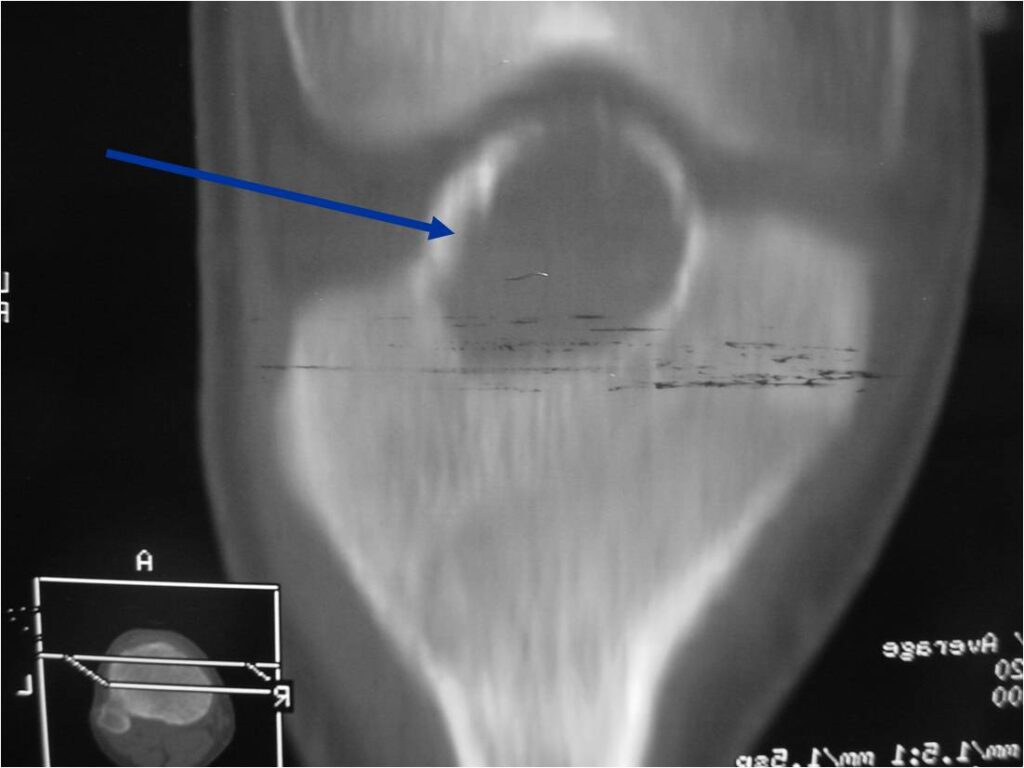

General Information Enchondroma is a benign indolent intramedullary hyaline cartilage neoplasm Accounts for 10% of all benign osseous tumors Limited growth, most lesions are less than 5 cm in maximal dimension Bones grow from a cartilaginous growth plate that...